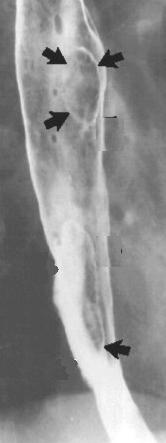

Image radiologique du transit

oesophagien d'un oesophagite caustique . C'est image

de stenose cicatricielle tres etendu de 2/3

inferierure oesophage |

Une autre cas de

oesophagite caustique . La lesion etendue le long

2/3 superiere de oesophage . Image radiologique du

transit oesophagien en OAD |

Oesophagite caustique 1/3 moyen de

oesophage avec aspect lesionaire c'est imsage

stenose cicatricielle a bord lisse de perdre

elasticite ( fleche blanche ) |